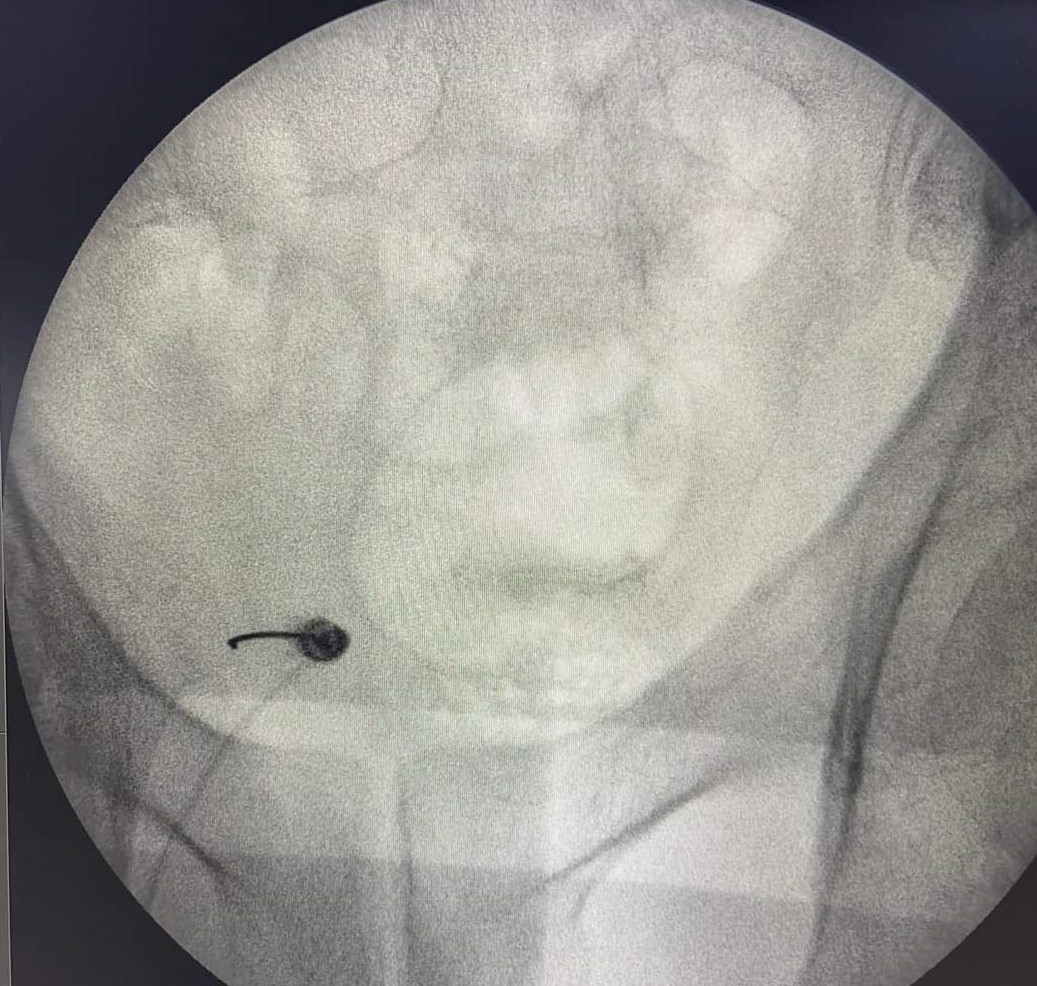

- Νευρόλυση με χρήση παλμικής ραδιοσυχνότητας υπό ακτινοσκοπική καθοδήγηση